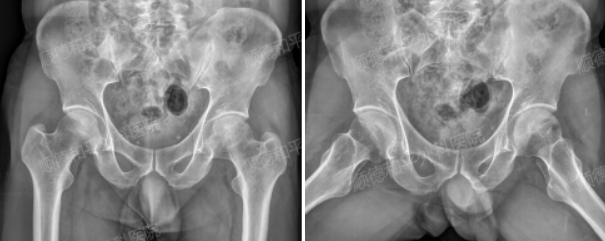

入院时骨盆正位片、蛙状位片

近期,一位49岁的男性患者因“左髋部疼痛不适2个月余”的困扰,慕名来到顺德和平外科医院手显微外科二区(骨髓炎专科)。患者回忆,大约2个月前,左侧髋部开始出现隐痛不适。起初,他并未太在意,然而随着时间推移,卧床翻身、起床改变体位以及行走时,左侧髋部的疼痛愈发明显,只有在平卧及休息时疼痛才有所缓解。虽然无双下肢麻木、胀痛等情况,但持续的疼痛严重影响了他的日常生活。此前,患者还曾就诊于当地医院,行X光片检查后提示双侧股骨头坏死。

患者入院后,我院医护人员立即为他进行了详细的查体:左下肢行走时暂未见明显跛行步态,左大腿、小腿肌肉也未见明显萎缩,双侧髋部外观尚对称。双髋部无明显叩痛,局部深压痛、内收肌止点压痛均为阴性,髋关节自主屈曲、外展、内收、外旋活动良好,左髋“4”字试验呈可疑阳性。双髋部皮肤无皮肤淤紫及破溃,下肢血运、感觉良好,膝踝关节自主活动良好,患者可自主完成髋关节、膝关节、踝关节屈伸动作及屈髋下蹲、穿鞋袜及下楼梯动作。